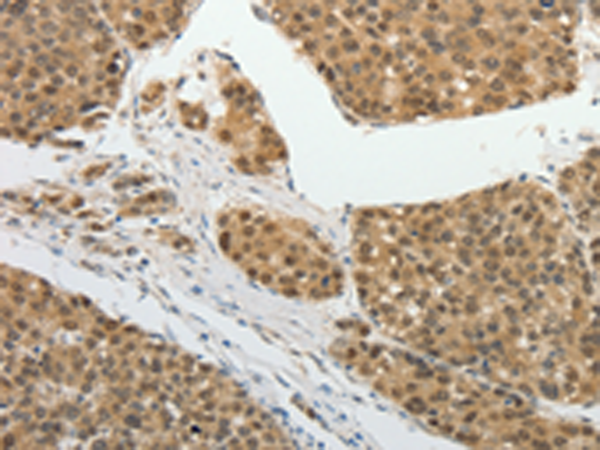

IHC positive control: |

Human liver cancer and human lung cancer |

IHC Recommend dilution: |

25-100 |